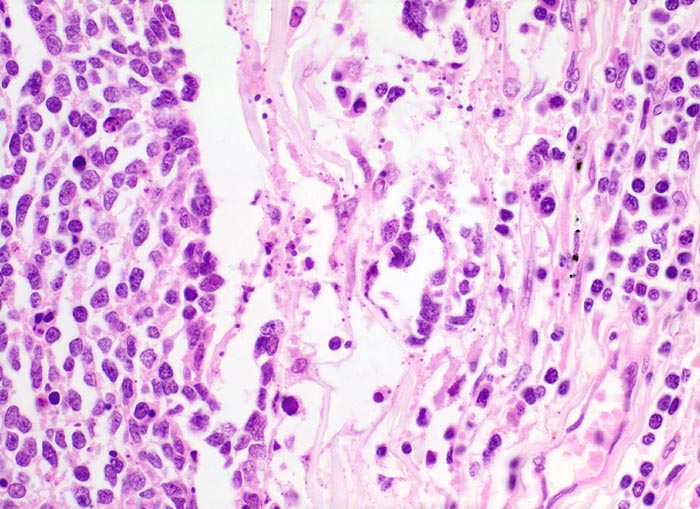

PathoPic – image database / PathoPic ID 4717 - kleinzelliges Bronchuskarzinom

kleinzelliges Bronchuskarzinom

Links im Bild die Tumorzellen des kleinzelligen Karzinoms. Die Kerne der Tumorzellen sind etwa dreimal so gross wie die der Lymphozyten rechts im Bild .

Inoperables metastasierendes Bronchuskarzinom. Nikotinabusus 70 Packyears.

Histologie

Vergrösserung